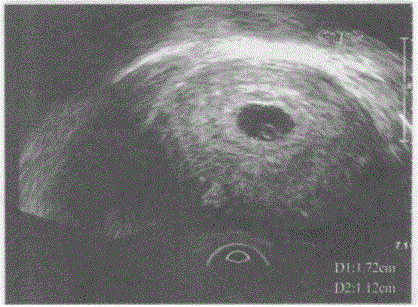

临床资料:女,25岁,自诉停经38天。超声综合描述:经阴道扫查子宫后位,形态饱满,肌层回声均匀,宫腔内见1.7cm×1.2cm×0.9cm孕囊,内见卵...

问题 临床资料:女,25岁,自诉停经38天。 超声综合描述:经阴道扫查子宫后位,形态饱满,肌层回声均匀,宫腔内见1.7cm×1.2cm×0.9cm孕囊,内见卵黄囊,未见胎芽及胎心搏动。 超声提示:

选项 A.宫内胚胎停育 B.宫内早孕 C.宫内假孕囊 D.宫腔积液

答案 B